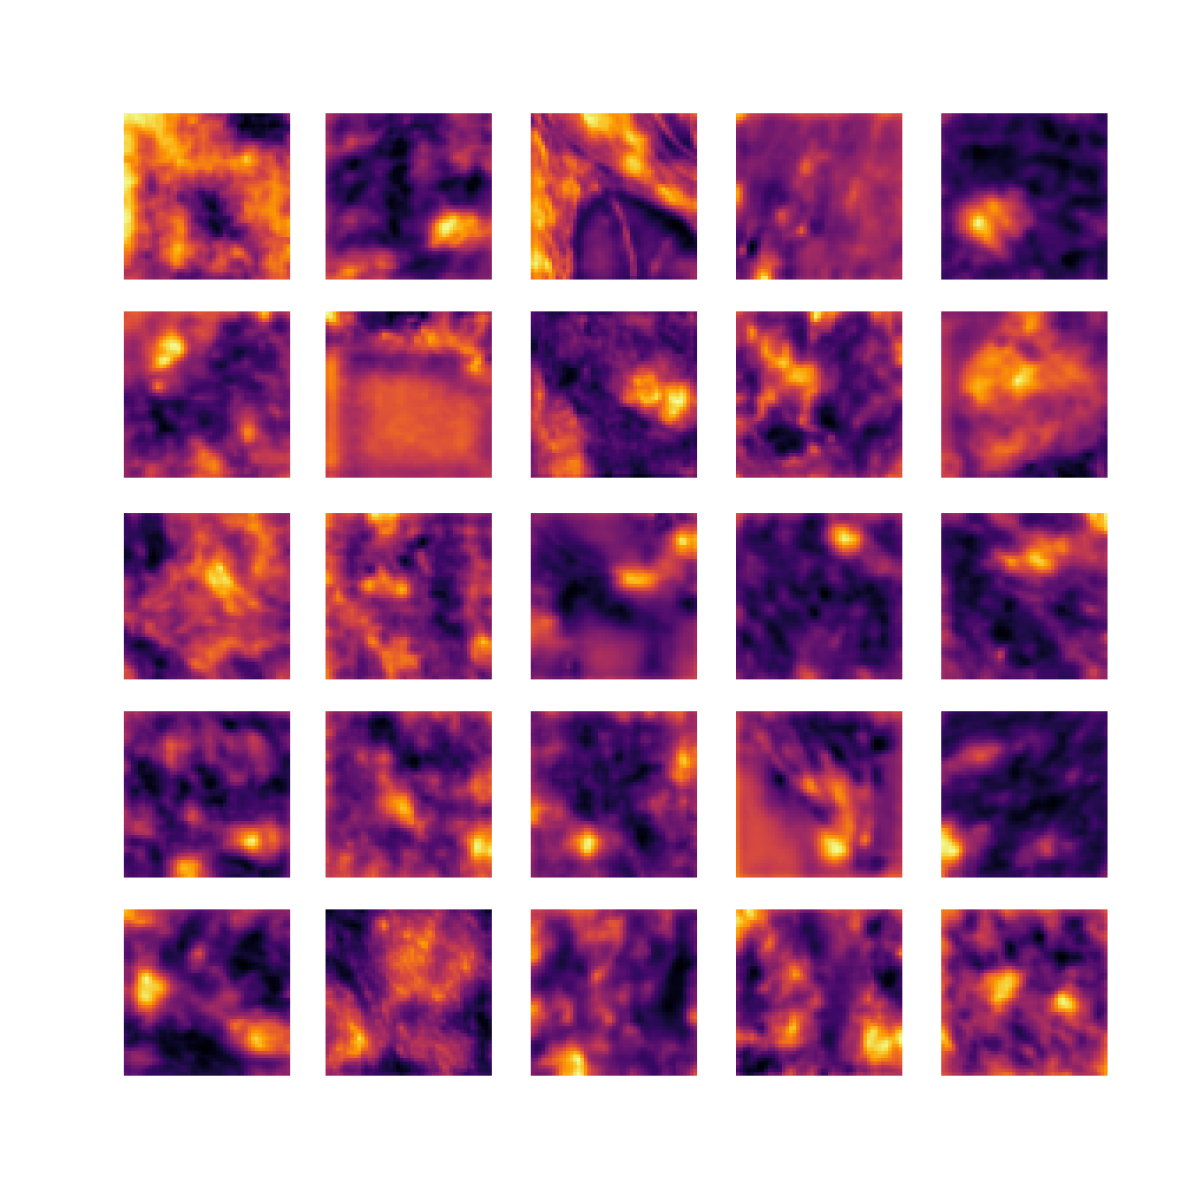

We also analyse the activation maps for each model using GradCAM as described in section S3. This offers more insight into the areas of the image which are contributing most heavily to the models’ representations. In Figure 4(b) we present some representative examples, however, a larger selection which was chosen at random is presented in Figures S10 to S25. The larger selection makes it easier to see the emergent patterns, including that privileged Siamese models tend to mainly identify features which are strongly present in both inputs, while unprivileged Siamese models tend to learn more diffuse features that are not specific to one cell phenotype or image region. TriDeNT ♆ incorporates both sets of features, learning both features specific to the privileged data and more the general features associated with unprivileged Siamese networks.

We can see in Figure 4(b) panel A that for ERG, the privileged Siamese model focuses almost exclusively on any nuclei which could be endothelial cells. As there are very few endothelial cells in the dataset, it could be an effective strategy to identify anything that could potentially be an endothelial cell to minimise the difference between the representations of the H&E model and the IF mask model. In the corresponding unprivileged Siamese image, we see that the model identifies some of these nuclei, albeit less strongly, but also focuses heavily on the other tissue and even the background, while strongly fixating on two spots of debris in the center of the image. This model has less ‘incentive’ to learn the weak features related to endothelial cells as these occur rarely and are not easy to detect, while more generic strong features such as the presence of connective tissue and the prevalence of background are more common and predictable from augmented images. We see that TriDeNT ♆ combines these two feature sets, strongly identifying nuclei while also identifying the connective tissue.

In panel C we see a similar pattern, with the privileged Siamese model fixating solely on the nuclei, while the TriDeNT ♆ model takes a more balanced approach. The unprivileged Siamese model appears to focus on a single cluster of nuclei while neglecting others, and similarly identifies an area of fibroblasts with its distinctive pattern but does not others.

In contrast to panels A and C which represent models with poor privileged Siamese results, panels B and D represent models whose privileged Siamese results were comparable to both TriDeNT ♆ and even the supervised baseline. It is therefore interesting to note that there are far more similarities between the privileged Siamese and TriDeNT ♆ models in both cases. Particularly in panel B, TriDeNT ♆ and the privileged Siamese model return virtually identical heatmaps, with both strongly identifying epithelial nuclei and neglecting the same areas of connective tissue. The unprivileged model in this case appears to focus solely on the centre of the image, giving a significantly different heatmap to the other panels.

Panel D again shows the previous pattern, with the privileged Siamese model identifying the features strongly present in the privileged data – fibroblasts – while neglecting the nuclei present. TriDeNT ♆ also strongly identifies the connective tissue, but, unlike the privileged Siamese model, does not completely neglect the nuclei. The unprivileged Siamese model primarily identifies background, and does not appear to identify the nuclei in this example.